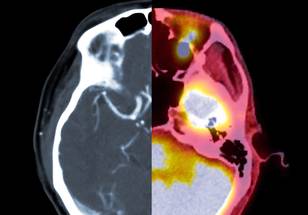

A new study, published in Biological Psychiatry, has revealed that mindfulness meditation engages distinct brain mechanisms to reduce pain compared to those of the placebo response. The study, conducted by researchers at University of California San Diego School of Medicine, used advanced brain imaging techniques to compare the pain-reducing effects of mindfulness meditation, a placebo cream and a “sham” mindfulness meditation in healthy participants.

The study found that mindfulness meditation produced significant reductions in pain intensity and pain unpleasantness ratings, and also reduced brain activity patterns associated with pain and negative emotions. In contrast, the placebo cream only reduced the brain activity pattern associated with the placebo effect, without affecting the person’s underlying experience of pain.